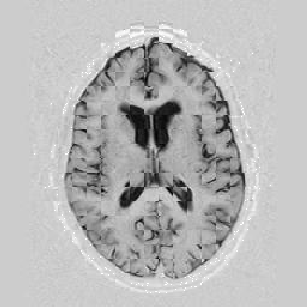

The results are shown for another pair of images in Figure [*].

Figure: Multi-scale NRR. From left to right, top then bottom: before NRR; after 5 iterations of NRR at level 2; after another 5 iterations of NRR at level 1.